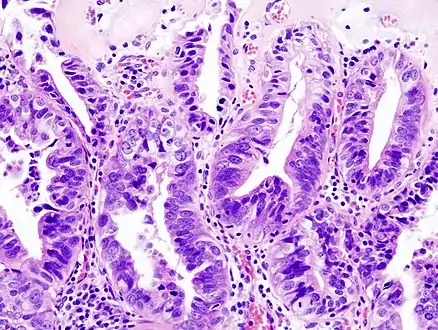

Gallbladder adenocarcinoma lymphatic invasion histopathology

Incidentally discovered gallbladder cancer (adenocarcinoma) following a cholecystectomy.

Gallbladder adenocarcinoma histopathology